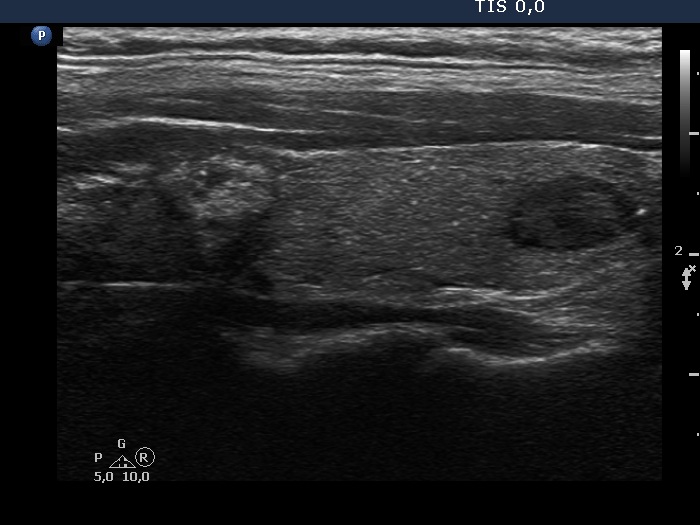

Ultrasonography. The thyroid was echonormal. There were two nodules in the left lobe. The upper lesion was a dominantly isoechoic nodule which had microcalcifications while the lower one was a hypoechoic nodule. There were numerous microcalcification relatively far from the primary tumor focus. The upper nodule was avascular while the lower one presented both intranodular and perinodular blood flow.

A conglomerate of lymph nodes was found 2 cm above the left lobe. The nodes did not have hilum but contained microcalcifications and presented irregular vascular pattern. (This was not noticed on the previous ultrasound examination.)